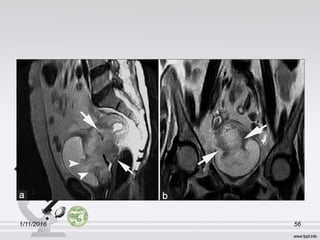

MRI:

1/11/2016 55

1/11/2016 56